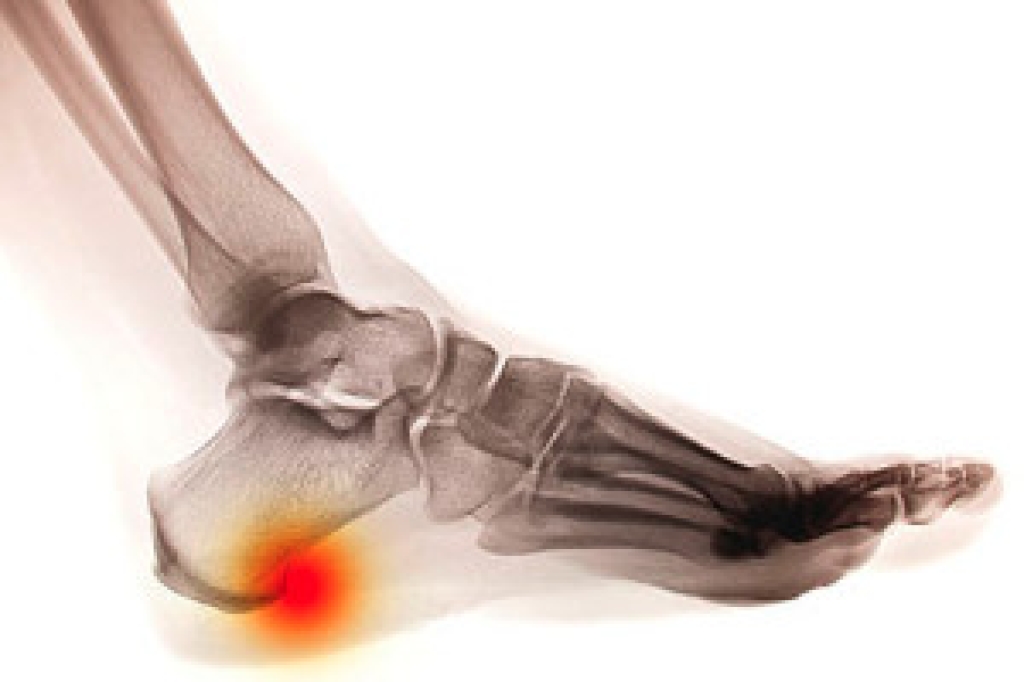

- Pain around the heel or arch area

- Swelling around the inside of the ankle

- Flat look to one or both feet